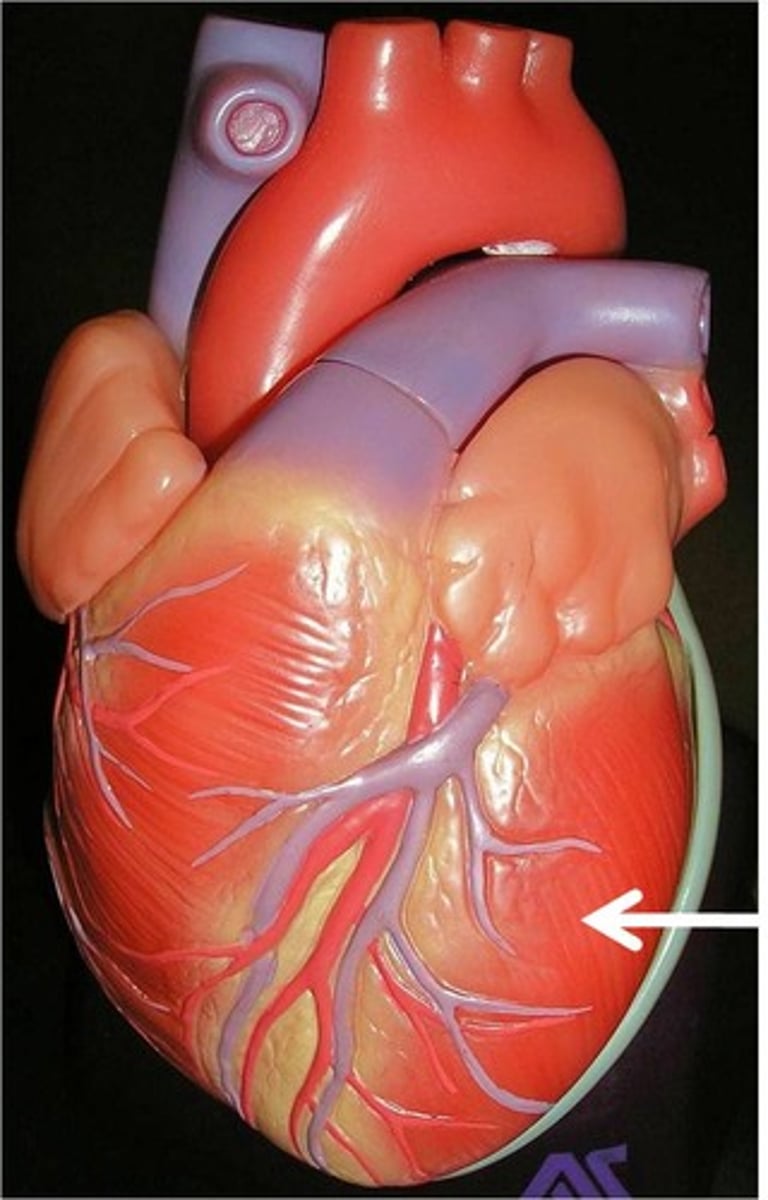

Great cardiac vein

structure.